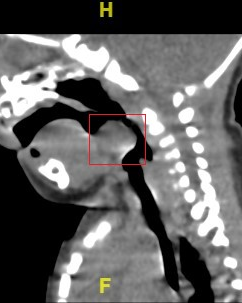

近日,我院收治了一名会厌囊肿的新生儿。患儿出生两天因呼吸困难转入我院,CT显示在会厌上方有一个23×17×11mm的囊性区,这就好比是一颗悬在气管入口的“定时炸弹”,随时威胁患儿的生命安全。

这个大的囊肿就是患儿呼吸困难的原因所在。病因诊断明确,下一步就是手术切除,手术方案定了,接下来要先过麻醉这一关。